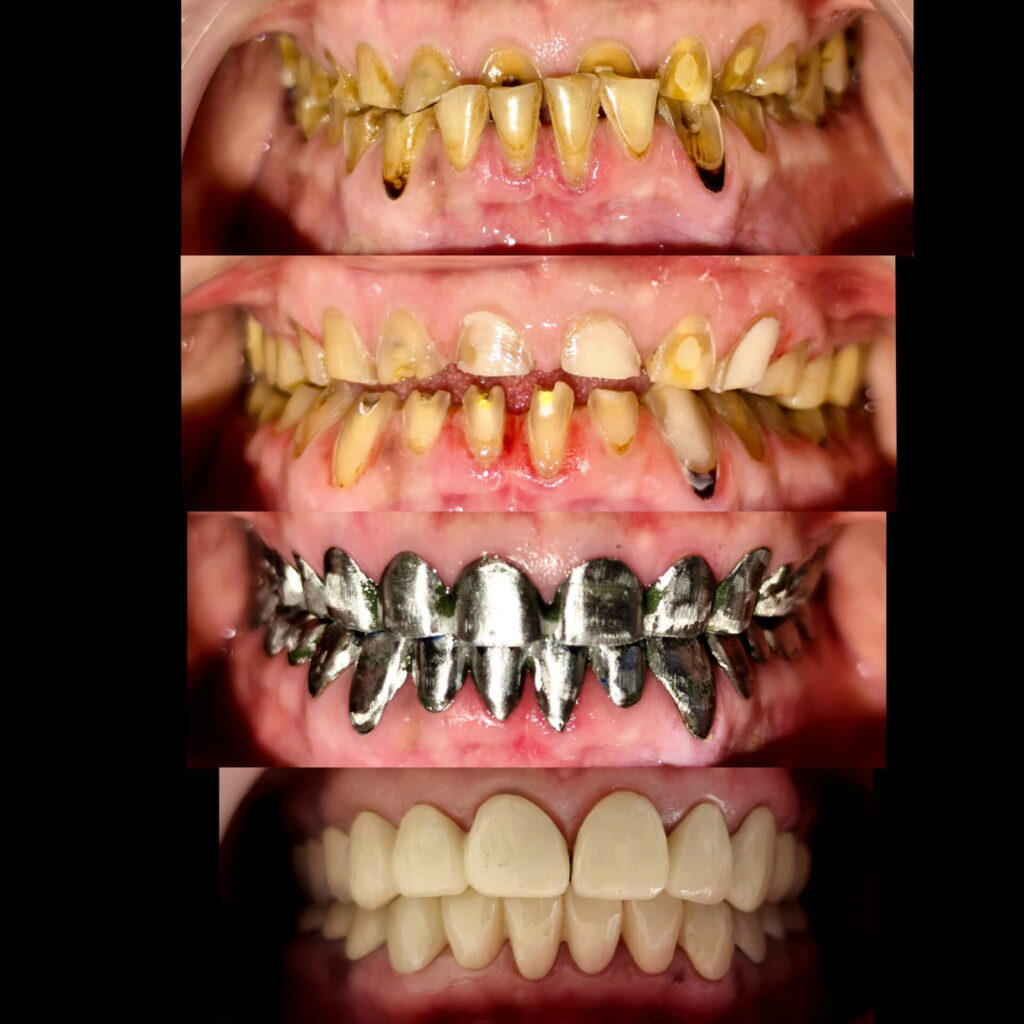

Full mouth rehabilitation of class 3 case with loss of vertical dimension